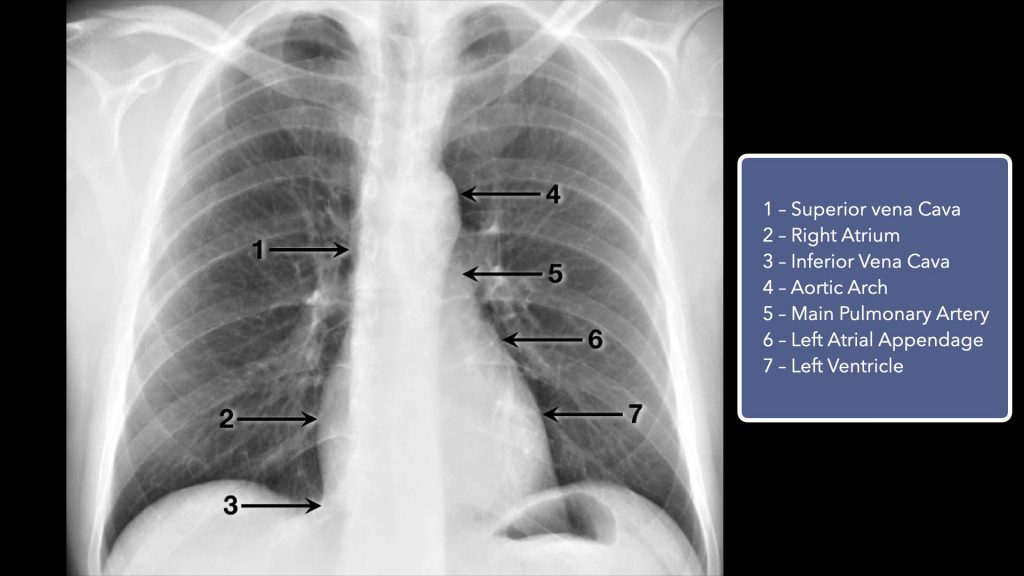

Cardiac

The heart width should be less than half the width of the thorax at its largest point. If the heart is larger than this, the patient has cardiomegaly. The cardiac border should include the superior vena cava, right atrium, inferior vena cava, aortic knot, left pulmonary artery, left atrial appendage, and also the left ventricle.